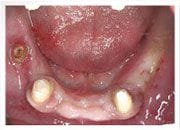

治療前